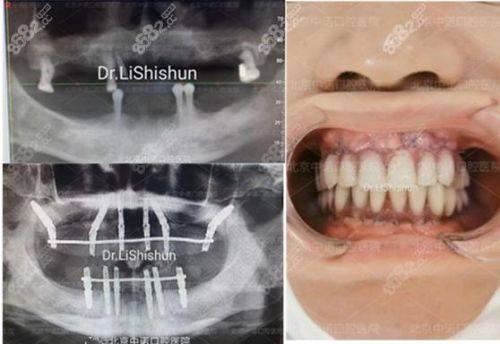

张女士-半口种植牙

"我因为年纪大了半口牙齿缺失,吃饭一直特别费劲,经朋友推荐找杨笑草医生做种植牙。杨医生耐心给我检查了牙槽骨情况,制定了all-on-4种植方案,手术过程比我想象的轻松特别多,修复得也快。现在我能正常吃一些稍硬的食物了,整个人的精神状态都好了不少,真的特别感谢杨医生的专精技术!"